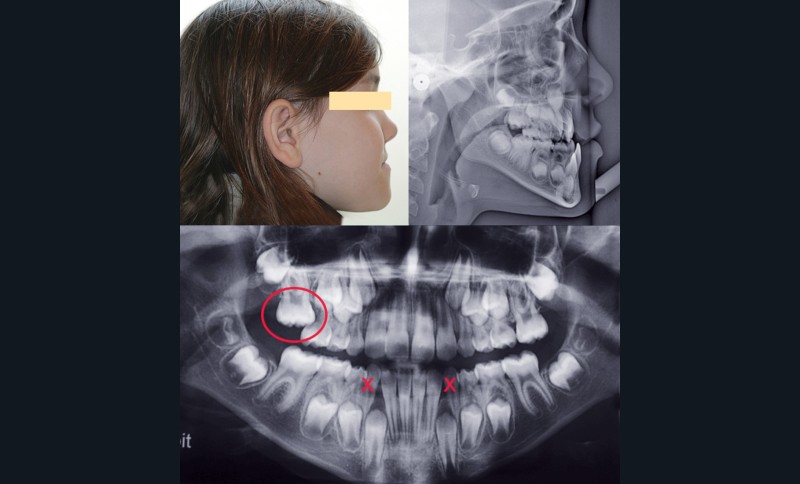

Cependant, la pose des plaques a été difficile du fait de la finesse du contrefort zygomatique et du peu de hauteur alvéolaire, en particulier au niveau du secteur I du fait de la rétention de la 16 (fig. 1).